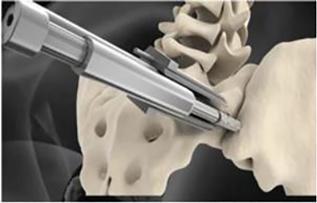

Tenon initiated its national commercial launch of The Catamaran System in October 2022 to address what we believe is a large market opportunity. The Catamaran System includes instruments and implants designed to prepare and fixate the SI-Joint for fusion. The Catamaran System is distinct from other competitive offerings in the following ways:

| ● | Transfixes the SI-Joint |

| ● | Inferior / Posterior Sacroiliac Fusion Approach |

| ● | Reduced Approach Morbidity |

| ● | Direct And Visualized Approach to the SI-Joint |

| ● | Single Implant Technique |

| ● | Insertion Trajectory Away from the Neural Foramen |

| ● | Insertion Trajectory Away from Major Lateral Vascular Structures |

| ● | Autologous Bone Grafting in the Ilium, Sacrum and Bridge |

| ● | Radiographic Confirmation of Bridging Bone Fusion of the SI-Joint |

The fixation device and its key features are shown below:

The Catamaran System is a singular implant designed with several proprietary components which allow for it to be explicitly formatted to address the SI-Joint with a single approach and implant. This contrasts with several competitive implant systems that require multiple approach pathways and implants to achieve fixation. In addition, the inferior-posterior approach is designed to be direct to the joint and through limited anatomical structures which may minimize the morbidity of the approach. The implant features a patented dual pontoon open cell design which enables the clinician to pack the pontoons with the patient’s own autologous bone designed to promote bone fusion across the joint. The Catamaran System is designed specially to resist vertical shear and rotation of the joint in which it was implanted, helping stabilize the joint in preparation for eventual fusion.

The instruments we have developed are proprietary to The Catamaran System and specifically designed to transfix the SI-Joint and facilitate an inferior-posterior approach that is unique to the system.